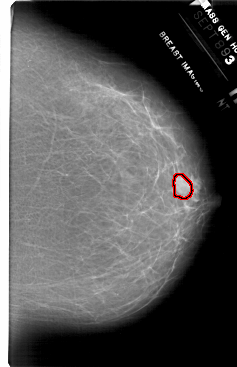

FILE: A_1717_1.RIGHT_MLO.OVERLAY

TOTAL_ABNORMALITIES 1

ABNORMALITY 1

LESION_TYPE MASS SHAPE LOBULATED MARGINS ILL_DEFINED

ASSESSMENT 4

SUBTLETY 3

PATHOLOGY BENIGN

TOTAL_OUTLINES 1

BOUNDARY

RIGHT_MLO LINES 6196 PIXELS_PER_LINE 4126 BITS_PER_PIXEL 12 RESOLUTION 43.5 OVERLAY